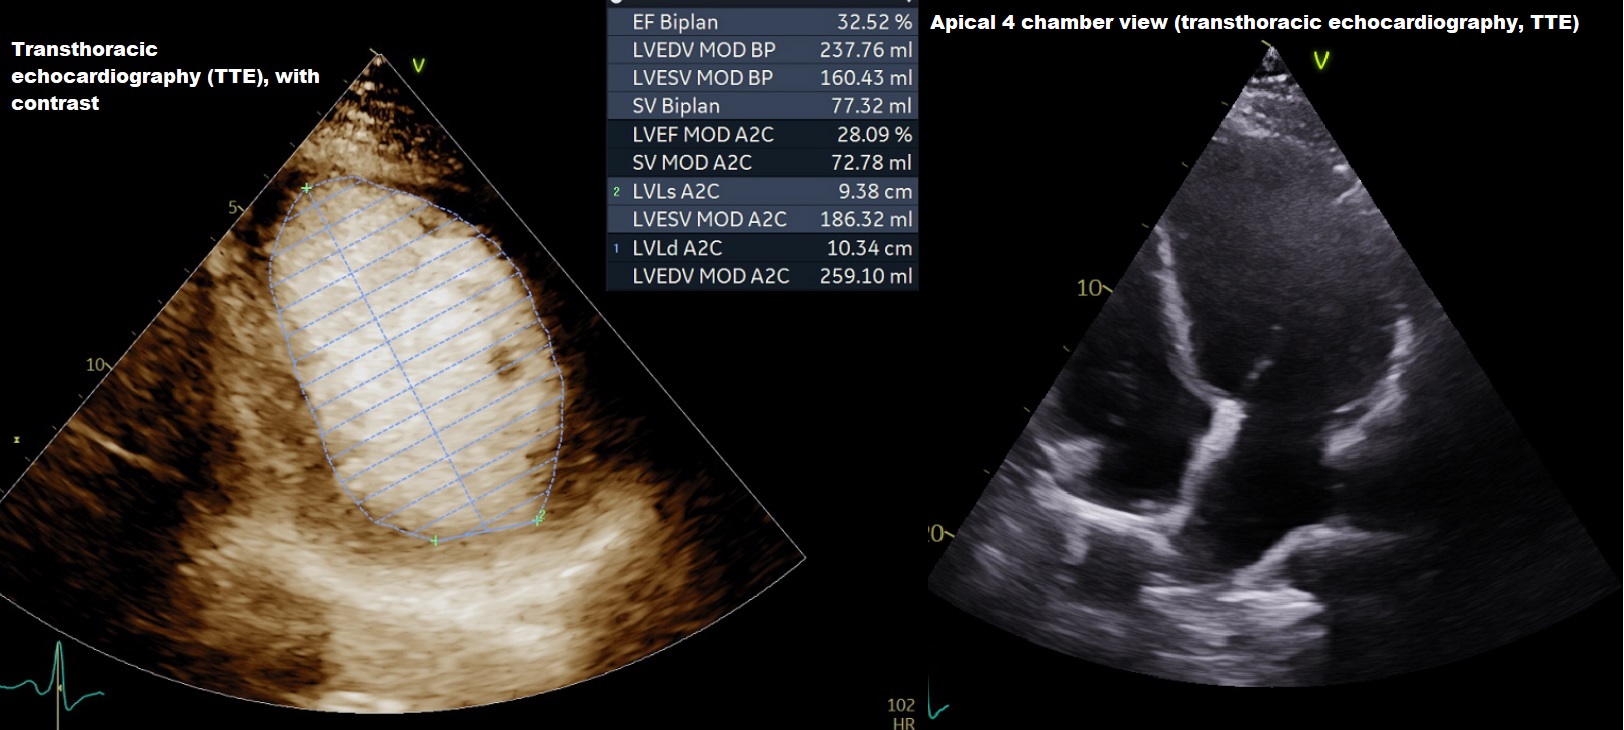

We report a case of a 52-year-old male who presented with progressive exertional dyspnea and clinical signs of heart failure. Electrocardiography showed no typical signs of ischemia. Laboratory findings showed significantly elevated N-terminal pro-B-type natriuretic peptide. Transthoracic echocardiography revealed severely impaired left ventricular ejection fraction. Coronary angiography was performed and showed a complex double coronary anomaly with an anomalous origin of the left coronary artery from the pulmonary artery with extensive collateralization from the right coronary artery supplying the left coronary system. Additionally, an anomalous origin of the circumflex artery from the right coronary artery with benign course, which is one of the most common coronary artery anomalies, was found. The diagnosis was subsequently confirmed by computed tomographic (CT) coronary angiogram with 3D reconstruction, which showed ectatic RCA arising from the right coronary sinus and the left descending artery arising from the pulmonary artery. Cardiac Magnetic Resonance (MR) demonstrated thinning of anterolateral wall of the left ventricle with sub endocardial delayed gadolinium enhancement.